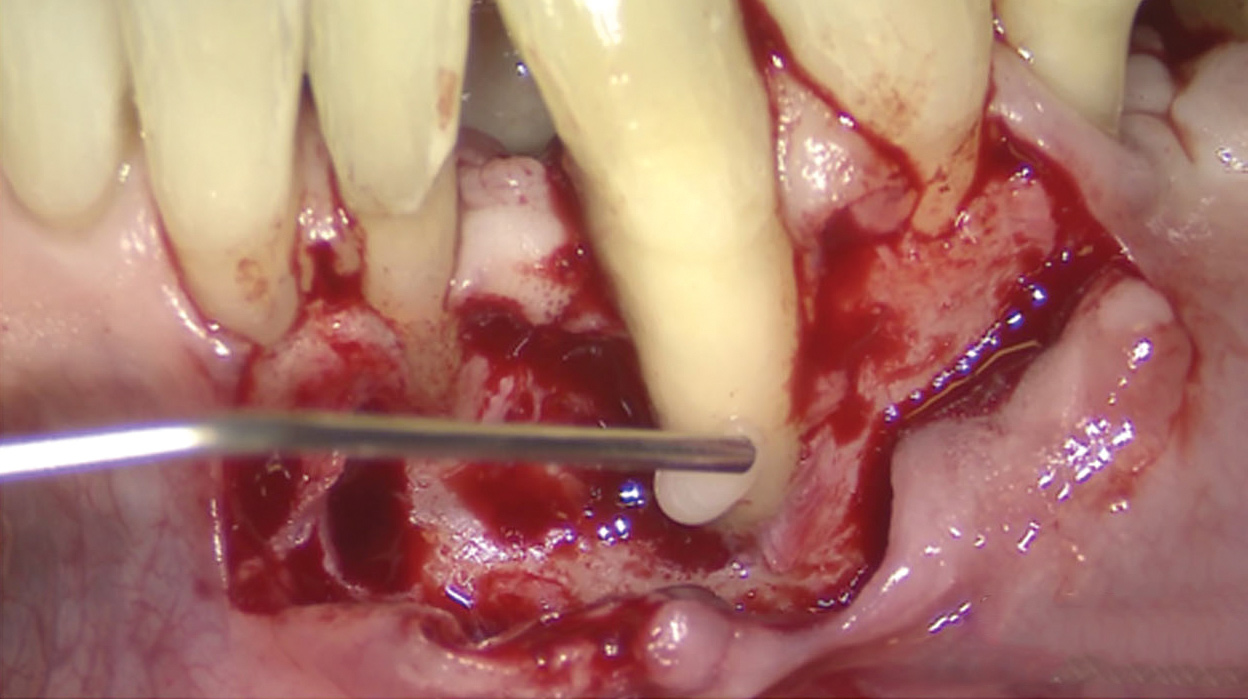

Fig 13. The scaffold was placed in the defect, where it remained for approximately 1 year. Fig 13: baseline; Fig 14: defect; Fig 15: scaffold matrix; Fig 16: scaffold placement; Fig 17: wound closure; Fig 18 through Fig 20: 2-month, 6-month, and 1-year postoperative, respectively. (Images reprinted with permission from Rasperini G, Pilipchuk SP, Flanagan CL, et al. J Dent Res. 2015;94[9 suppl]:153S-157S.)

Figure 13

Fig 14. The scaffold was placed in the defect, where it remained for approximately 1 year. Fig 13: baseline; Fig 14: defect; Fig 15: scaffold matrix; Fig 16: scaffold placement; Fig 17: wound closure; Fig 18 through Fig 20: 2-month, 6-month, and 1-year postoperative, respectively. (Images reprinted with permission from Rasperini G, Pilipchuk SP, Flanagan CL, et al. J Dent Res. 2015;94[9 suppl]:153S-157S.)

Figure 14